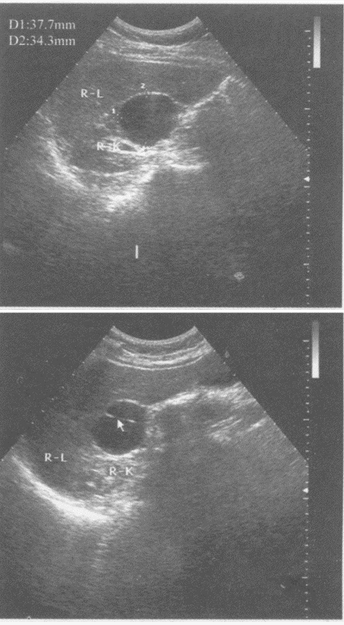

临床资料:男,49岁,常规体检。超声综合描述:右肾中部可见3.8cm×3.4cm无回声区,形态规则,向外突起,内见完整分隔(箭头所指),包膜完整,后方声加强。

超声提示()

A:右肾癌

B:右肾盂积水

C:右肾囊肿

D:肝囊肿